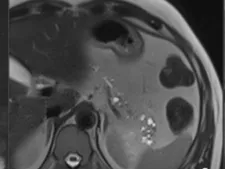

During this fellowship CT/MR technique as well as the different pathologies of the pancreas will be shown, in an interactive way, trying to illustrate the best technique according to the different clinical fields.

The preparation of the patient, optimal CT/MR pancreatic protocols with special emphasis on MR/MRCP also with secretin test.

Most frequent as well as rare pancreatic pathologies will be shown. Diagnosis, differential diagnosis, staging and assessment of therapeutic response will be illustrated.